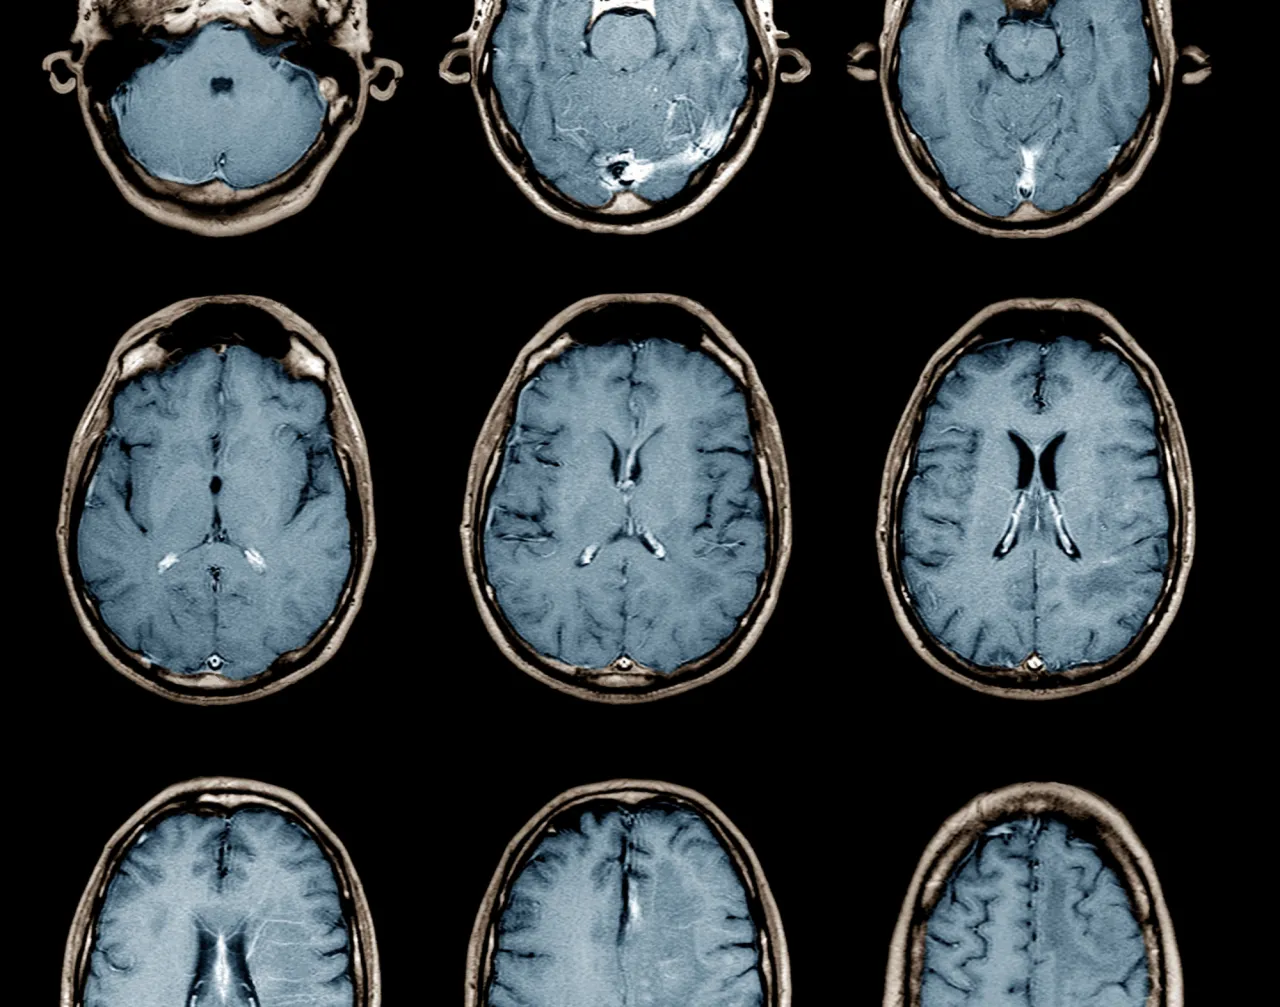

Czepki EEG i skanery fMRI: jak odczytać myśli bez operacji?

Na drugim biegunie mamy metody nieinwazyjne, które pozwalają na mierzenie aktywności mózgu bez konieczności operacji. Najpopularniejszą z nich jest elektroencefalografia (EEG), wykorzystująca czepki z elektrodami umieszczane na skórze głowy. Inna to funkcjonalny rezonans magnetyczny (fMRI), który mierzy zmiany w przepływie krwi w mózgu. Te technologie mierzą aktywność mózgu z zewnątrz, co oznacza, że są bezpieczniejsze, ale zazwyczaj oferują niższą precyzję niż implanty. Mimo to, systemy przenośne z EEG stają się coraz dokładniejsze w testach osiągają już 40% skuteczności w tłumaczeniu myśli na mowę, z celem osiągnięcia 90%.